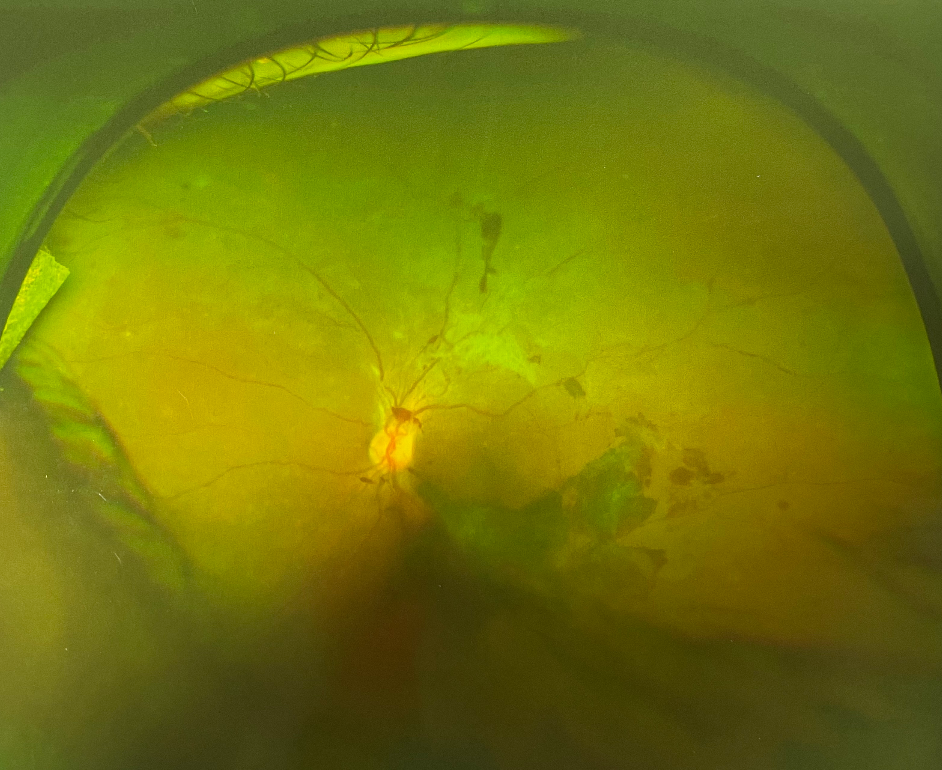

眼底出血是常見的眼科疾病之一,是眼底視網(wǎng)膜血管的病變引起的。正常情況下,血液在人體的血管內(nèi)流動,不會溢出,但如果身體出了問題,無論是眼睛局部的問題還是全身的病變,在眼睛血管里流動的血液就會溢出來,溢在視網(wǎng)膜上,這就形成了眼底出血。

造成眼底出血的原因有很多,如果治療不及時還會引起失明的嚴重后果,所以一定要早發(fā)現(xiàn)早治療。

眼底出血如何治療?

目前多用眼內(nèi)注射聯(lián)合激光治療,以藥物治療為輔。

眼內(nèi)注射主要治療伴有黃斑水腫的患者,治療后大部分黃斑水腫消退,視力提高。

眼底激光治療主要是延緩病情發(fā)展,防治新生血管的產(chǎn)生或消退新生血管,避免更嚴重的視力下降。